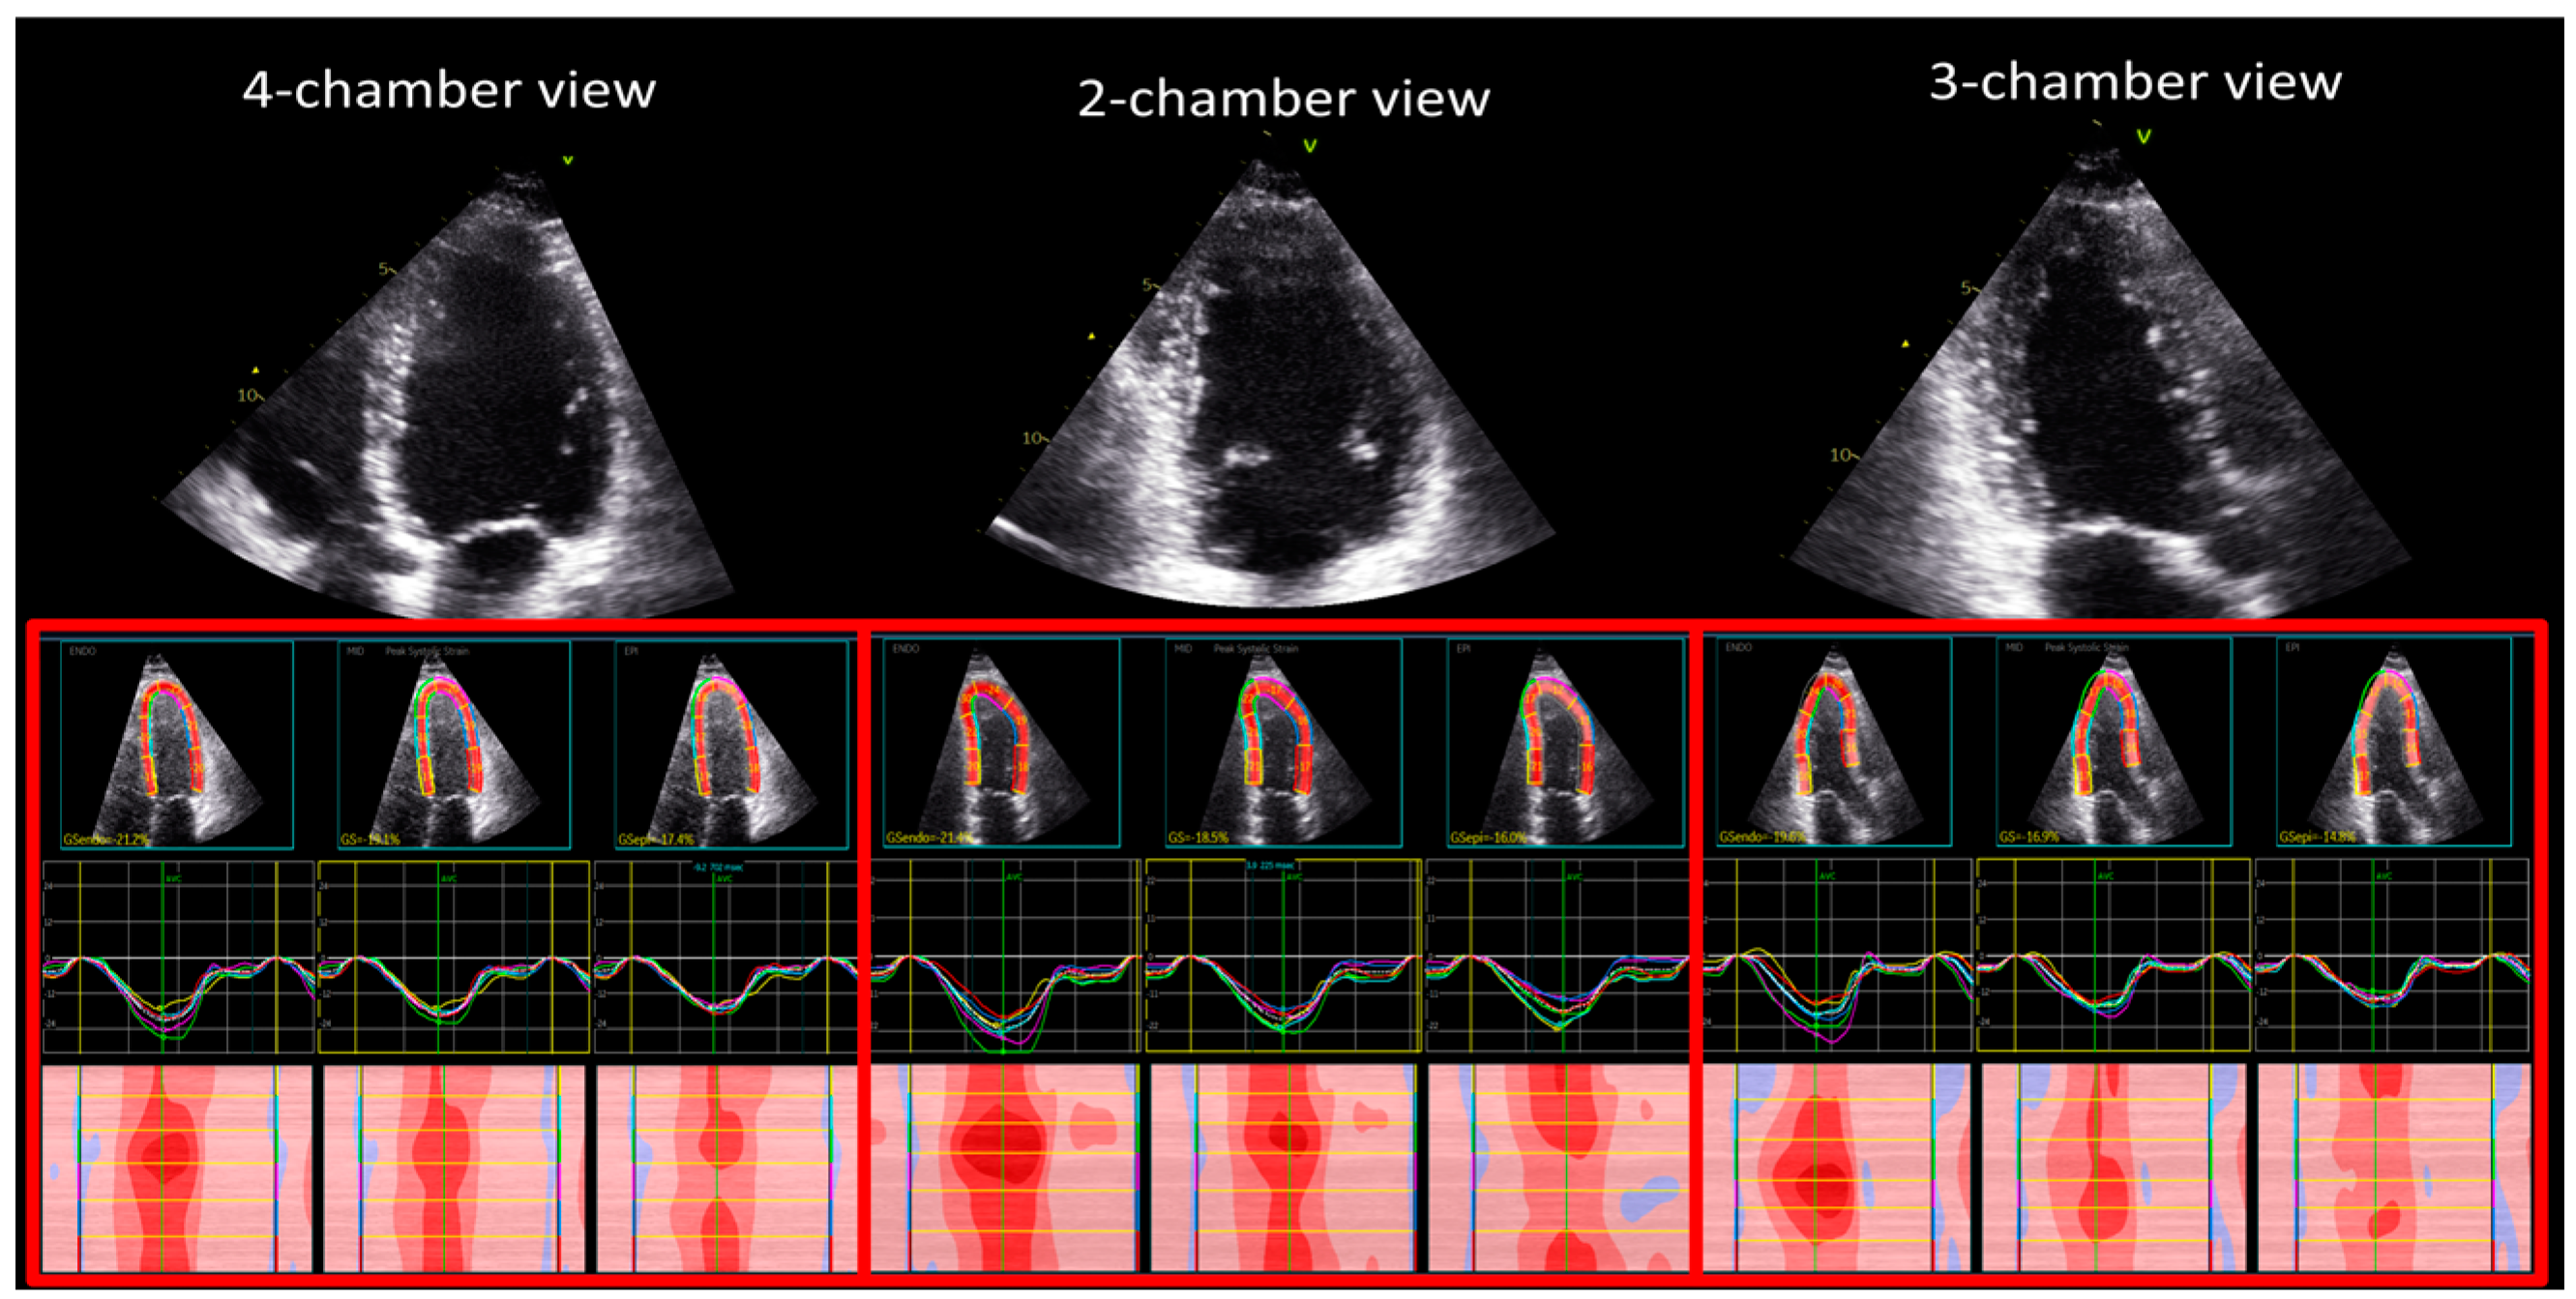

2.2. Two-Dimensional Echocardiographic Strain Measurements

3.3. Segmental Longitudinal Strain

4.2. Segmental Longitudinal Strain